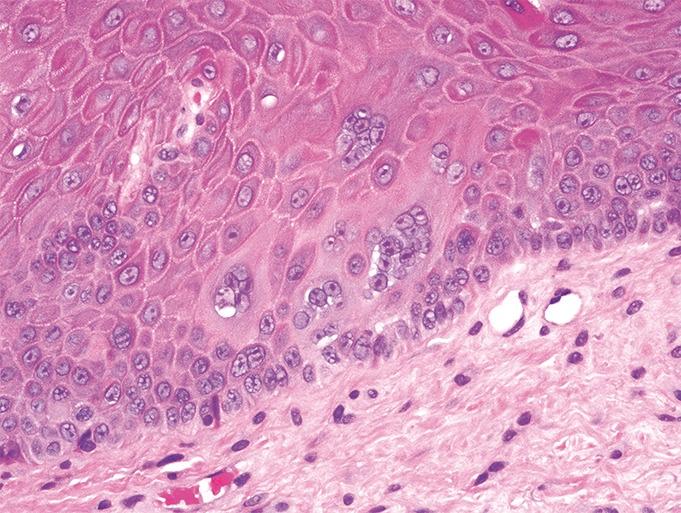

Multinucleated keratinocytes (also known as multinucleated epidermal giant cells) are a frequently overlooked histological finding in noninfectious inflammatory dermatoses. They are sometimes found in conditions characterized by chronic rubbing and pruritus, such as lichen simplex chronicus or prurigo nodularis, and may be a helpful clue in making the clinical diagnosis. This finding must be differentiated from other conditions characterized by multinucleated keratinocytes on histopathology, specifically herpes simplex, varicella zoster, or measles viral infections. The authors present a case series of 2 patients with unique clinical noninfectious diagnoses but similar histopathologic findings on biopsy. The histopathologic findings on both cases demonstrated multinucleated keratinocytes, which were related to manipulation of the epidermis.

多核角质形成细胞(也称为多核表皮巨细胞)是在非感染性炎症性皮肤病中经常被忽视的组织学表现。它们有时见于以慢性摩擦和瘙痒为特征的疾病,如慢性单纯性苔藓或结节性痒疹,可能是做出临床诊断的有用线索。这一表现必须与组织病理学上以多核角质形成细胞为特征的其他疾病相鉴别,特别是单纯疱疹、水痘带状疱疹或麻疹病毒感染。作者报告了一个病例系列,其中2例患者有独特的临床非感染性诊断,但活检时组织病理学表现相似。两例病例的组织病理学表现均显示多核角质形成细胞,这与表皮的人为因素有关。